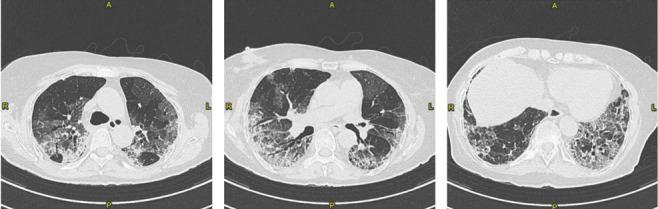

Platypnea-Orthodeoxia Syndrome (POS) is a clinical entity defined as positional dyspnoea (platypnea) and arterial desaturation (orthodeoxia) that occurs when sitting or standing up and usually resolves by lying down. Up to April 25th 2021, eleven cases of POS after SARS-CoV-2 pneumonia have been reported on Pubmed. Accordingly, SARS-CoV-2 infection may be considered as an emergent cause of POS due to an increase in ventilation/perfusion (V/Q) mismatch. In this article we provide an update on the patient with POS after fibrotic evolution of SARS-CoV-2 interstitial pneumonia, which we previously reported and we discuss the case reports of POS due to SARS-CoV-2 infection.

体位性呼吸困难-低氧血症综合征(POS)是一种临床病症,定义为当坐立或站立时出现呼吸困难(体位性呼吸困难)和动脉血氧饱和度降低(低氧血症),而当躺下时通常会缓解。截至 2021 年 4 月 25 日,在 Pubmed 上已报告了 11 例 SARS-CoV-2 肺炎后 POS 病例。因此,由于通气/血流(V/Q)不匹配增加,SARS-CoV-2 感染可被视为 POS 的一个新出现病因。在本文中,我们对先前报道的纤维化演变后的 SARS-CoV-2 间质性肺炎后出现 POS 的患者进行了更新,并讨论了因 SARS-CoV-2 感染而出现 POS 的病例报告。